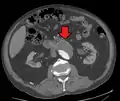

An abdominal aortic aneurysm is usually diagnosed by physical exam, abdominal ultrasound, or CT scan. Plain abdominal radiographs may show the outline of an aneurysm when its walls are calcified. However, the outline will be visible by X-ray in less than half of all aneurysms. Ultrasonography is used to screen for aneurysms and to determine their size if present. Additionally, free peritoneal fluid can be detected. It is noninvasive and sensitive, but the presence of bowel gas or obesity may limit its usefulness. CT scan has nearly 100% sensitivity for an aneurysm and is also useful in preoperative planning, detailing the anatomy and possibility for endovascular repair. In the case of suspected rupture, it can also reliably detect retroperitoneal fluid. Alternative less often used methods for visualization of an aneurysm include MRI and angiography.

Abdominal aortic endoprosthesis, CT scan, original aneurysm marked in blue